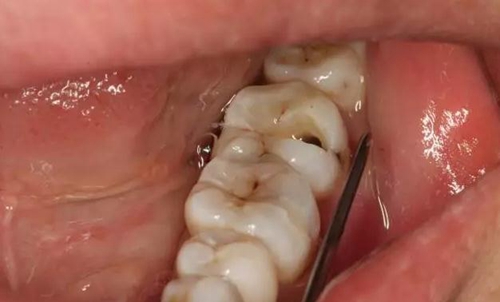

圖2.  37牙冠基本完好,松動Ⅰ度。合面有一開髓孔被棉球覆蓋,頰側牙齦輕度紅腫。

2.jpg